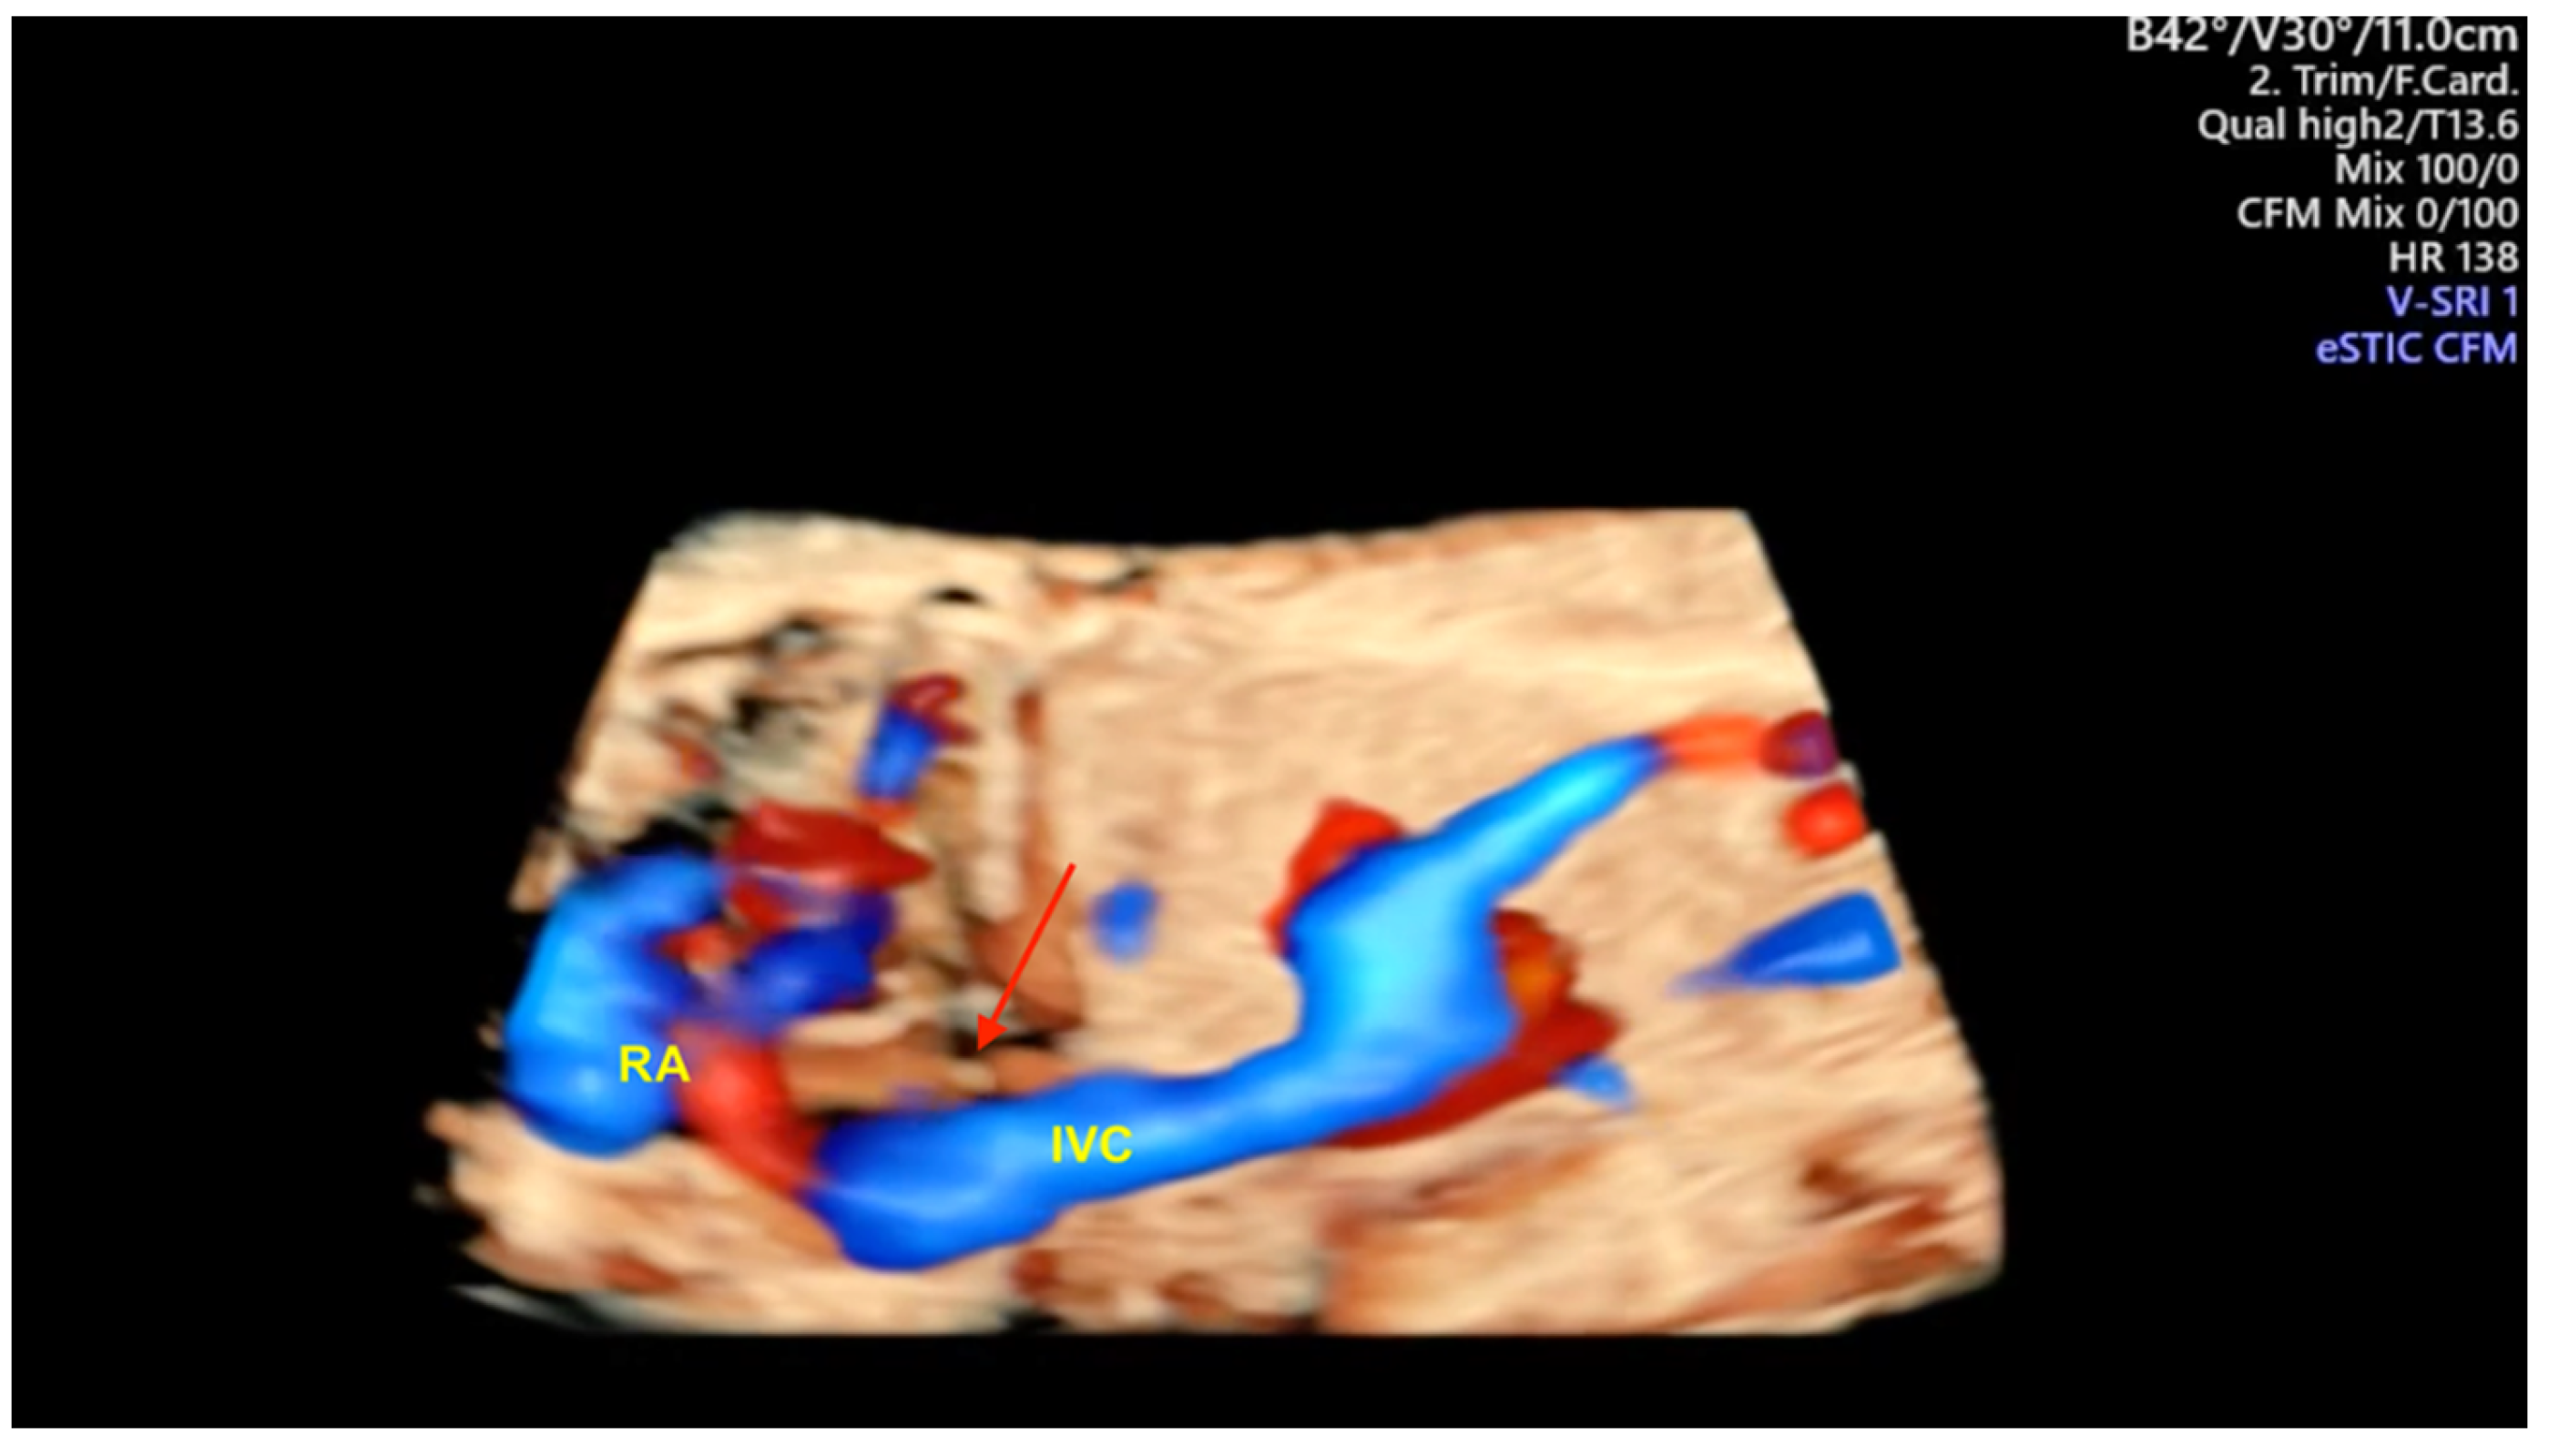

- Tie HX, Ma B, Zhang DC, Li TG. Prenatal diagnosis of fetal inferior vena cava malformation using HDlive flow combined with spatiotemporal image correlation. Echocardiography. 2022, 39, 685–690.

- Li TG, Ma B, Gao YH, Zhang RH, Li PL, Da ZQ. Prenatal diagnosis of total anomalous pulmonary venous connection using 2D and HDlive flow combined with spatiotemporal image correlation. Echocardiography. 2022, 39, 1269–1275.